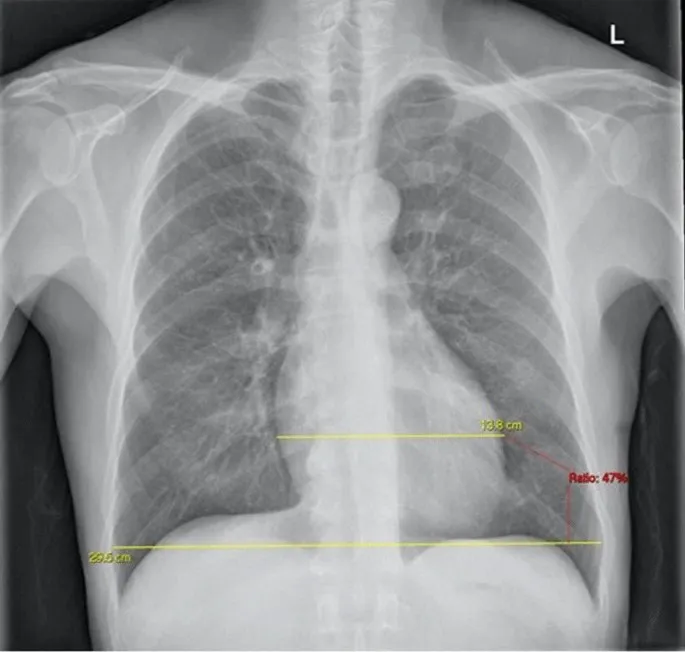

- Cardiothoracic Ratio (CTR):

- Normally < 0.5 on a posteroanterior (PA) film.

- Calculated as maximal cardiac width divided by maximal thoracic width.

- A CTR > 0.5 suggests cardiomegaly.

- A cardiothoracic ratio >0.5 on a PA chest X-ray is a key sign of cardiomegaly.